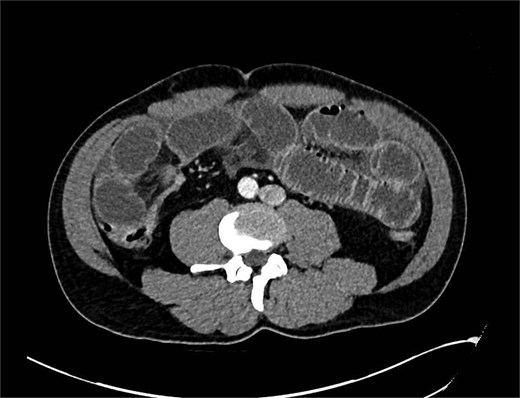

A computed tomography (CT) scan was performed which showed: ‘The findings raise the possibility of a closed loop SBO involving the ileal small bowel in the right iliac fossa. There is a slightly thickened segment of ileum with mildly reduced enhancement with a transition point proximally and distally identified. There is no evidence of perforation currently’ (Figs 1 and 2).

CT showing abnormality in right iliac fossa with dilated bowel loops.